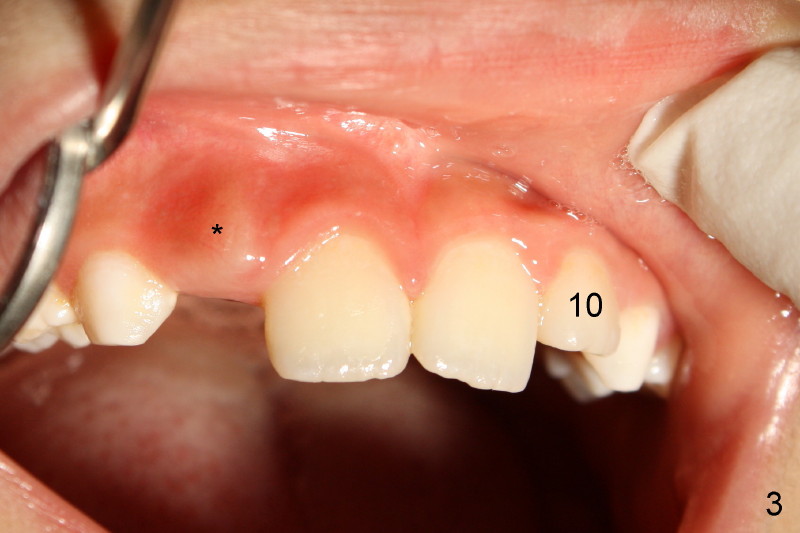

Panramic X-ray was taken when Edward was 6 years 5 months old (Fig.1). His parents and he himself found that the upper right lateral did not erupt at the age of 9 years 2 months (Fig.2-4: *). Gingivectomy was performed using soft tissue laser to expose the incisal edge of the lateral. Five months later, the lateral has erupted partially (Fig.5-8), but the family is concerned about the cosmetic issue. It appears that the upper midline has shifted to the right (Fig.6). Periapical film is planned to take to confirm the relationship between the canine and the lateral.